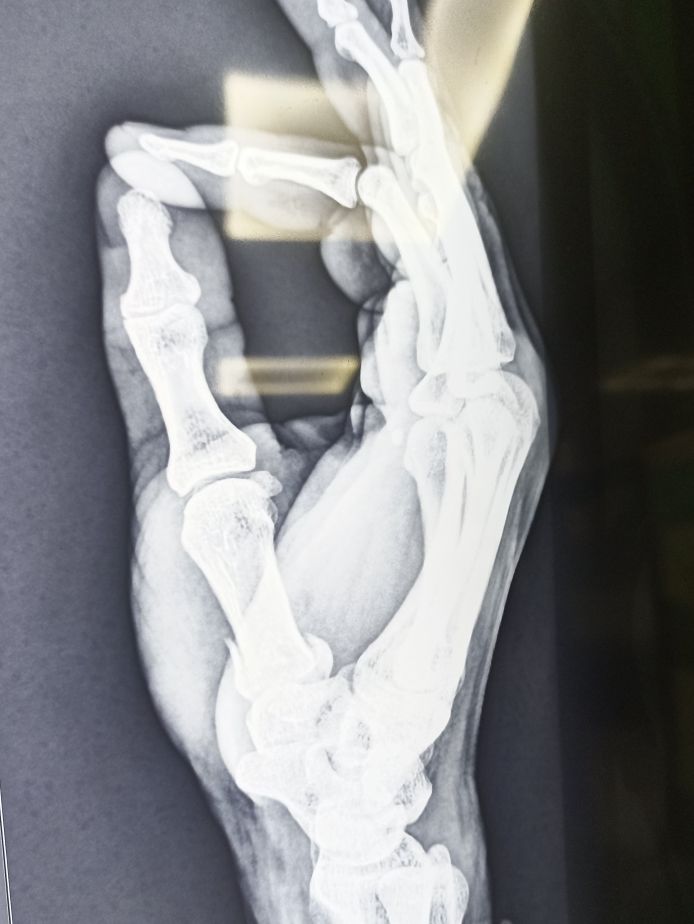

K Wire Procedure . K wire (kirschner wire) is passed through the skin then transversely through the bone and out the other side of the limb. K wire fixation of hand fractures. The wire is then attached to some form of traction so that the pull is applied directly to bone. Introduced in 1909 by martin kirschner, the. They can be placed percutaneously (through the skin) or can be buried beneath the skin. Each method has its advantages and disadvantages. These wires can be drilled through the bone to hold the fragments in place.

These wires can be drilled through the bone to hold the fragments in place. Introduced in 1909 by martin kirschner, the. They can be placed percutaneously (through the skin) or can be buried beneath the skin. K wire fixation of hand fractures. K wire (kirschner wire) is passed through the skin then transversely through the bone and out the other side of the limb. Each method has its advantages and disadvantages. The wire is then attached to some form of traction so that the pull is applied directly to bone.